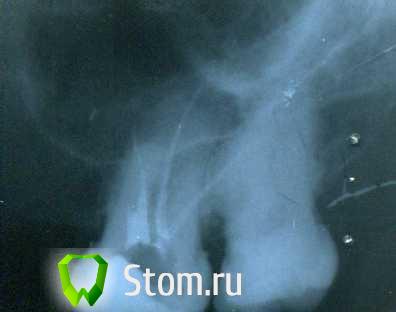

kukolenOk Опубликовано 23 февраля, 2012 Поделиться Опубликовано 23 февраля, 2012 (изменено) зуб 1.6 до лечения. зуб 1.6 в процессе лечения. зуб 1.6 после леченияDs: хронический пульпит 1.6 зубав процессе лечения сломала инструмент в м-щ канале, но смогла обойти его в последствии эндочаком, итог на снимке. Зуб пойдет под коронку. возьмутся ли за такой? Изменено 23 февраля, 2012 пользователем kukolenOk Ссылка на комментарий

Scrabble Опубликовано 23 февраля, 2012 Поделиться Опубликовано 23 февраля, 2012 (изменено) Видно несколько проблем: перфорация МБ корня и создание ложного канала, недостаточное расширение каналов и как следствие их неудовлетворительная обтурация. Если у Вас только 02 конус в наличии, то обрабатывайте до 55/02. Не до апекса, естественно. Плюс теперь надо пройти МБ по анатомическому курсу и закрыть перфорацию. В МБ ногу вкладки ни в коем разе... Изменено 23 февраля, 2012 пользователем Scrabble Ссылка на комментарий

DokDent Опубликовано 23 февраля, 2012 Поделиться Опубликовано 23 февраля, 2012 А вообще снимок лучше переделать.+ к вышесказанному в медиальном скорей всего 2 канала. Ссылка на комментарий